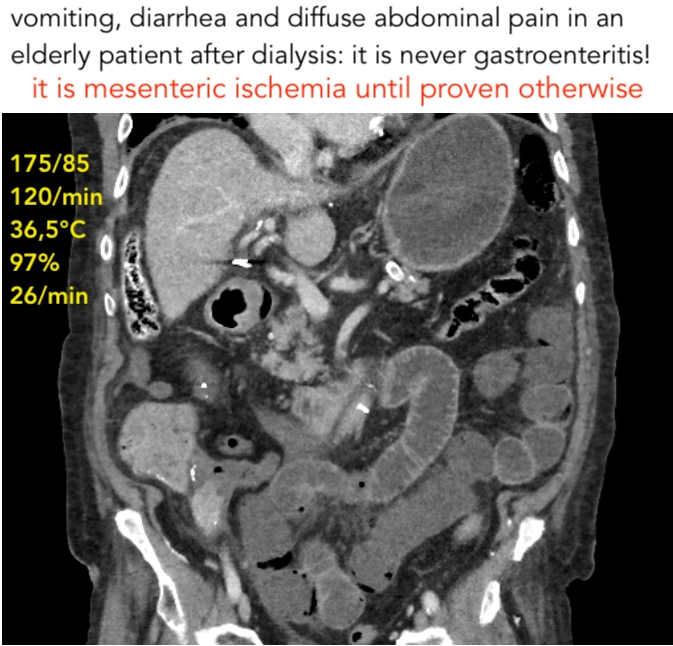

NO gastroenteritis